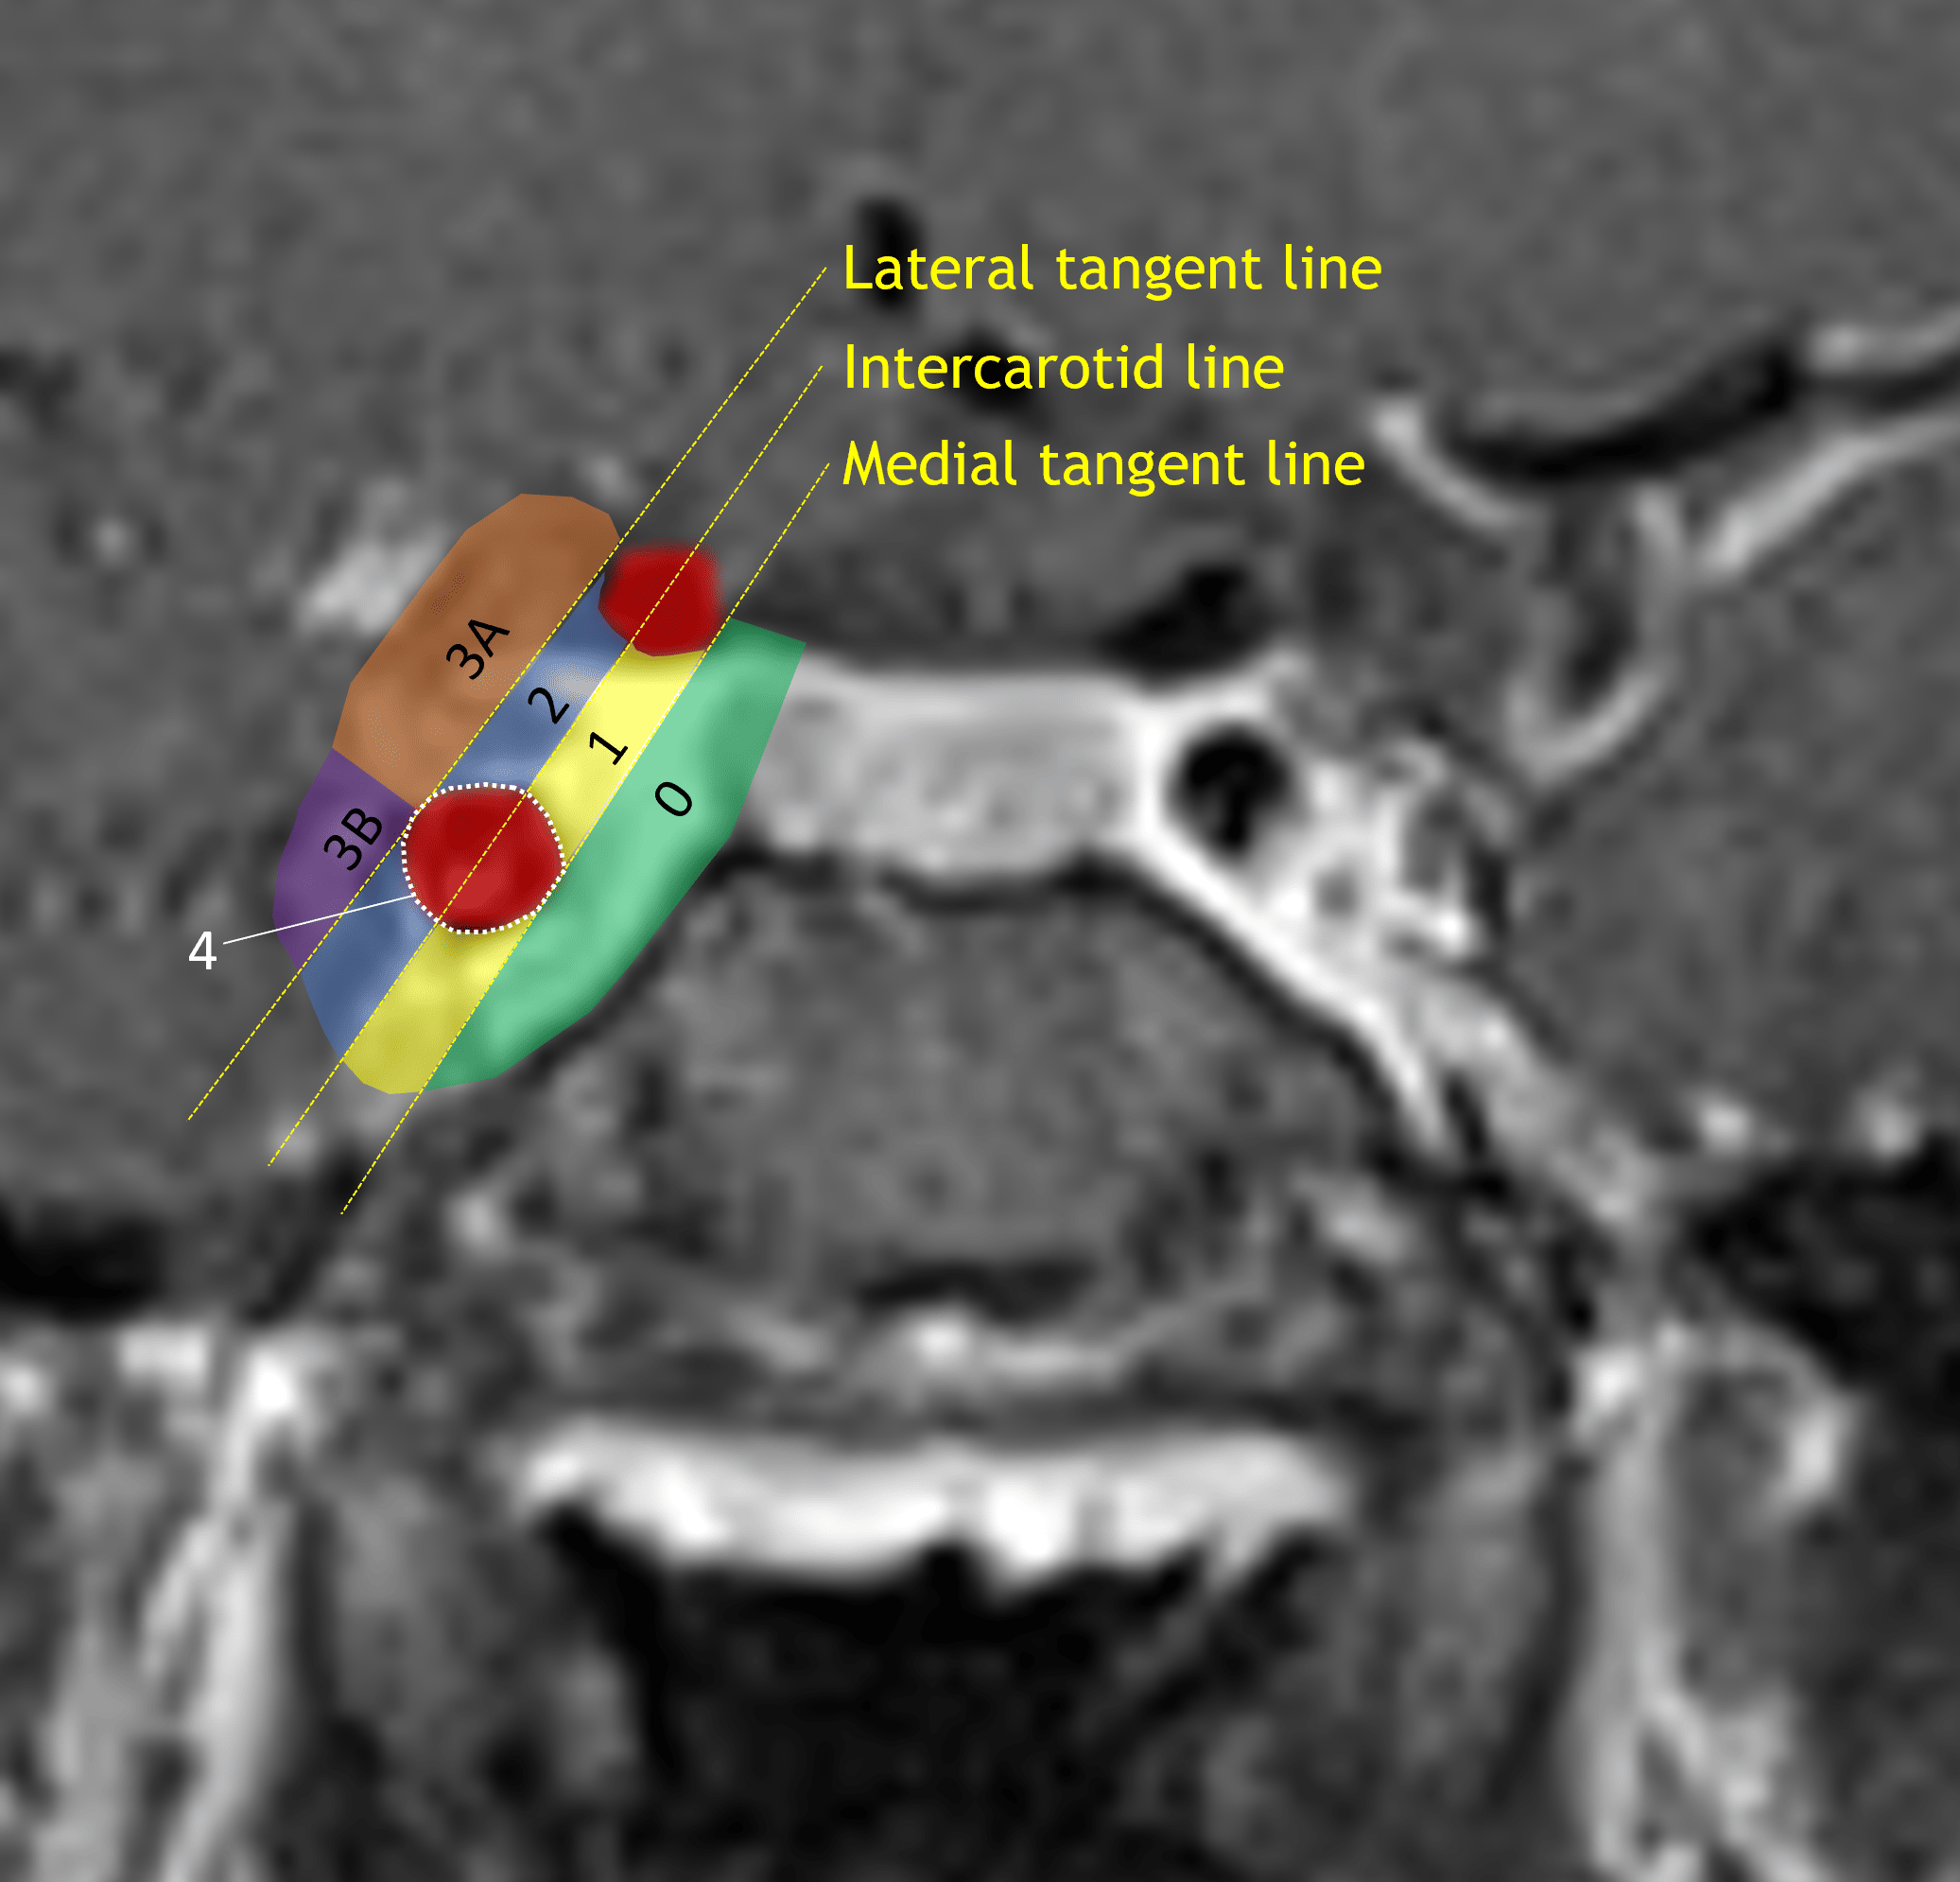

- Tumor extends beyond the lateral carotid tangent line on the right and slightly beyond the intercarotid line on the left with partial encasement of the bilateral internal carotid arteries

Knosp classification system.